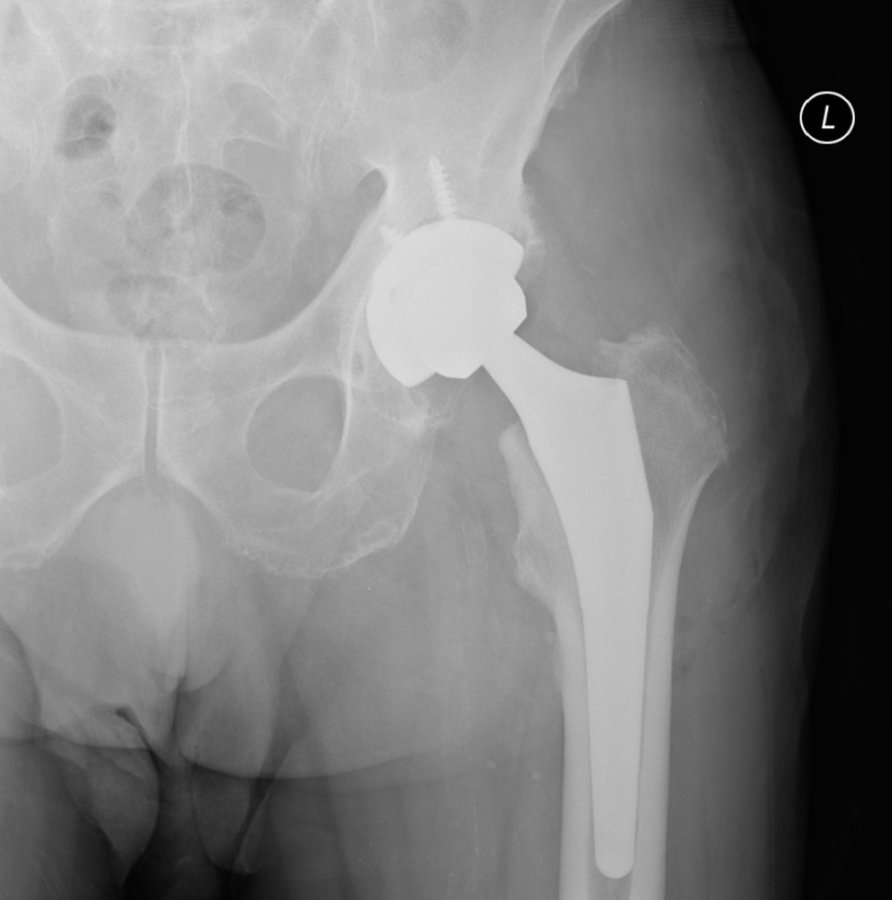

حول كاريا جراحة العظام وإعادة التأهيل عيادة كاريا جراحة العظام وإعادة التأهيل في موغلا ، تركيا تقدم رعاية العظام عالية الجودة ، بما في ذلك العلاجات الجراحية وغير الجراحية من قبل Assoc. البروفيسور الدكتور جيم يالين KILIN وفريقه. وهم متخصصون في الصدمات والإصابات الرياضية وجراحات تقويم المفاصل ، ولديهم خبرة في العلاج الطبيعي لإعادة التأهيل.